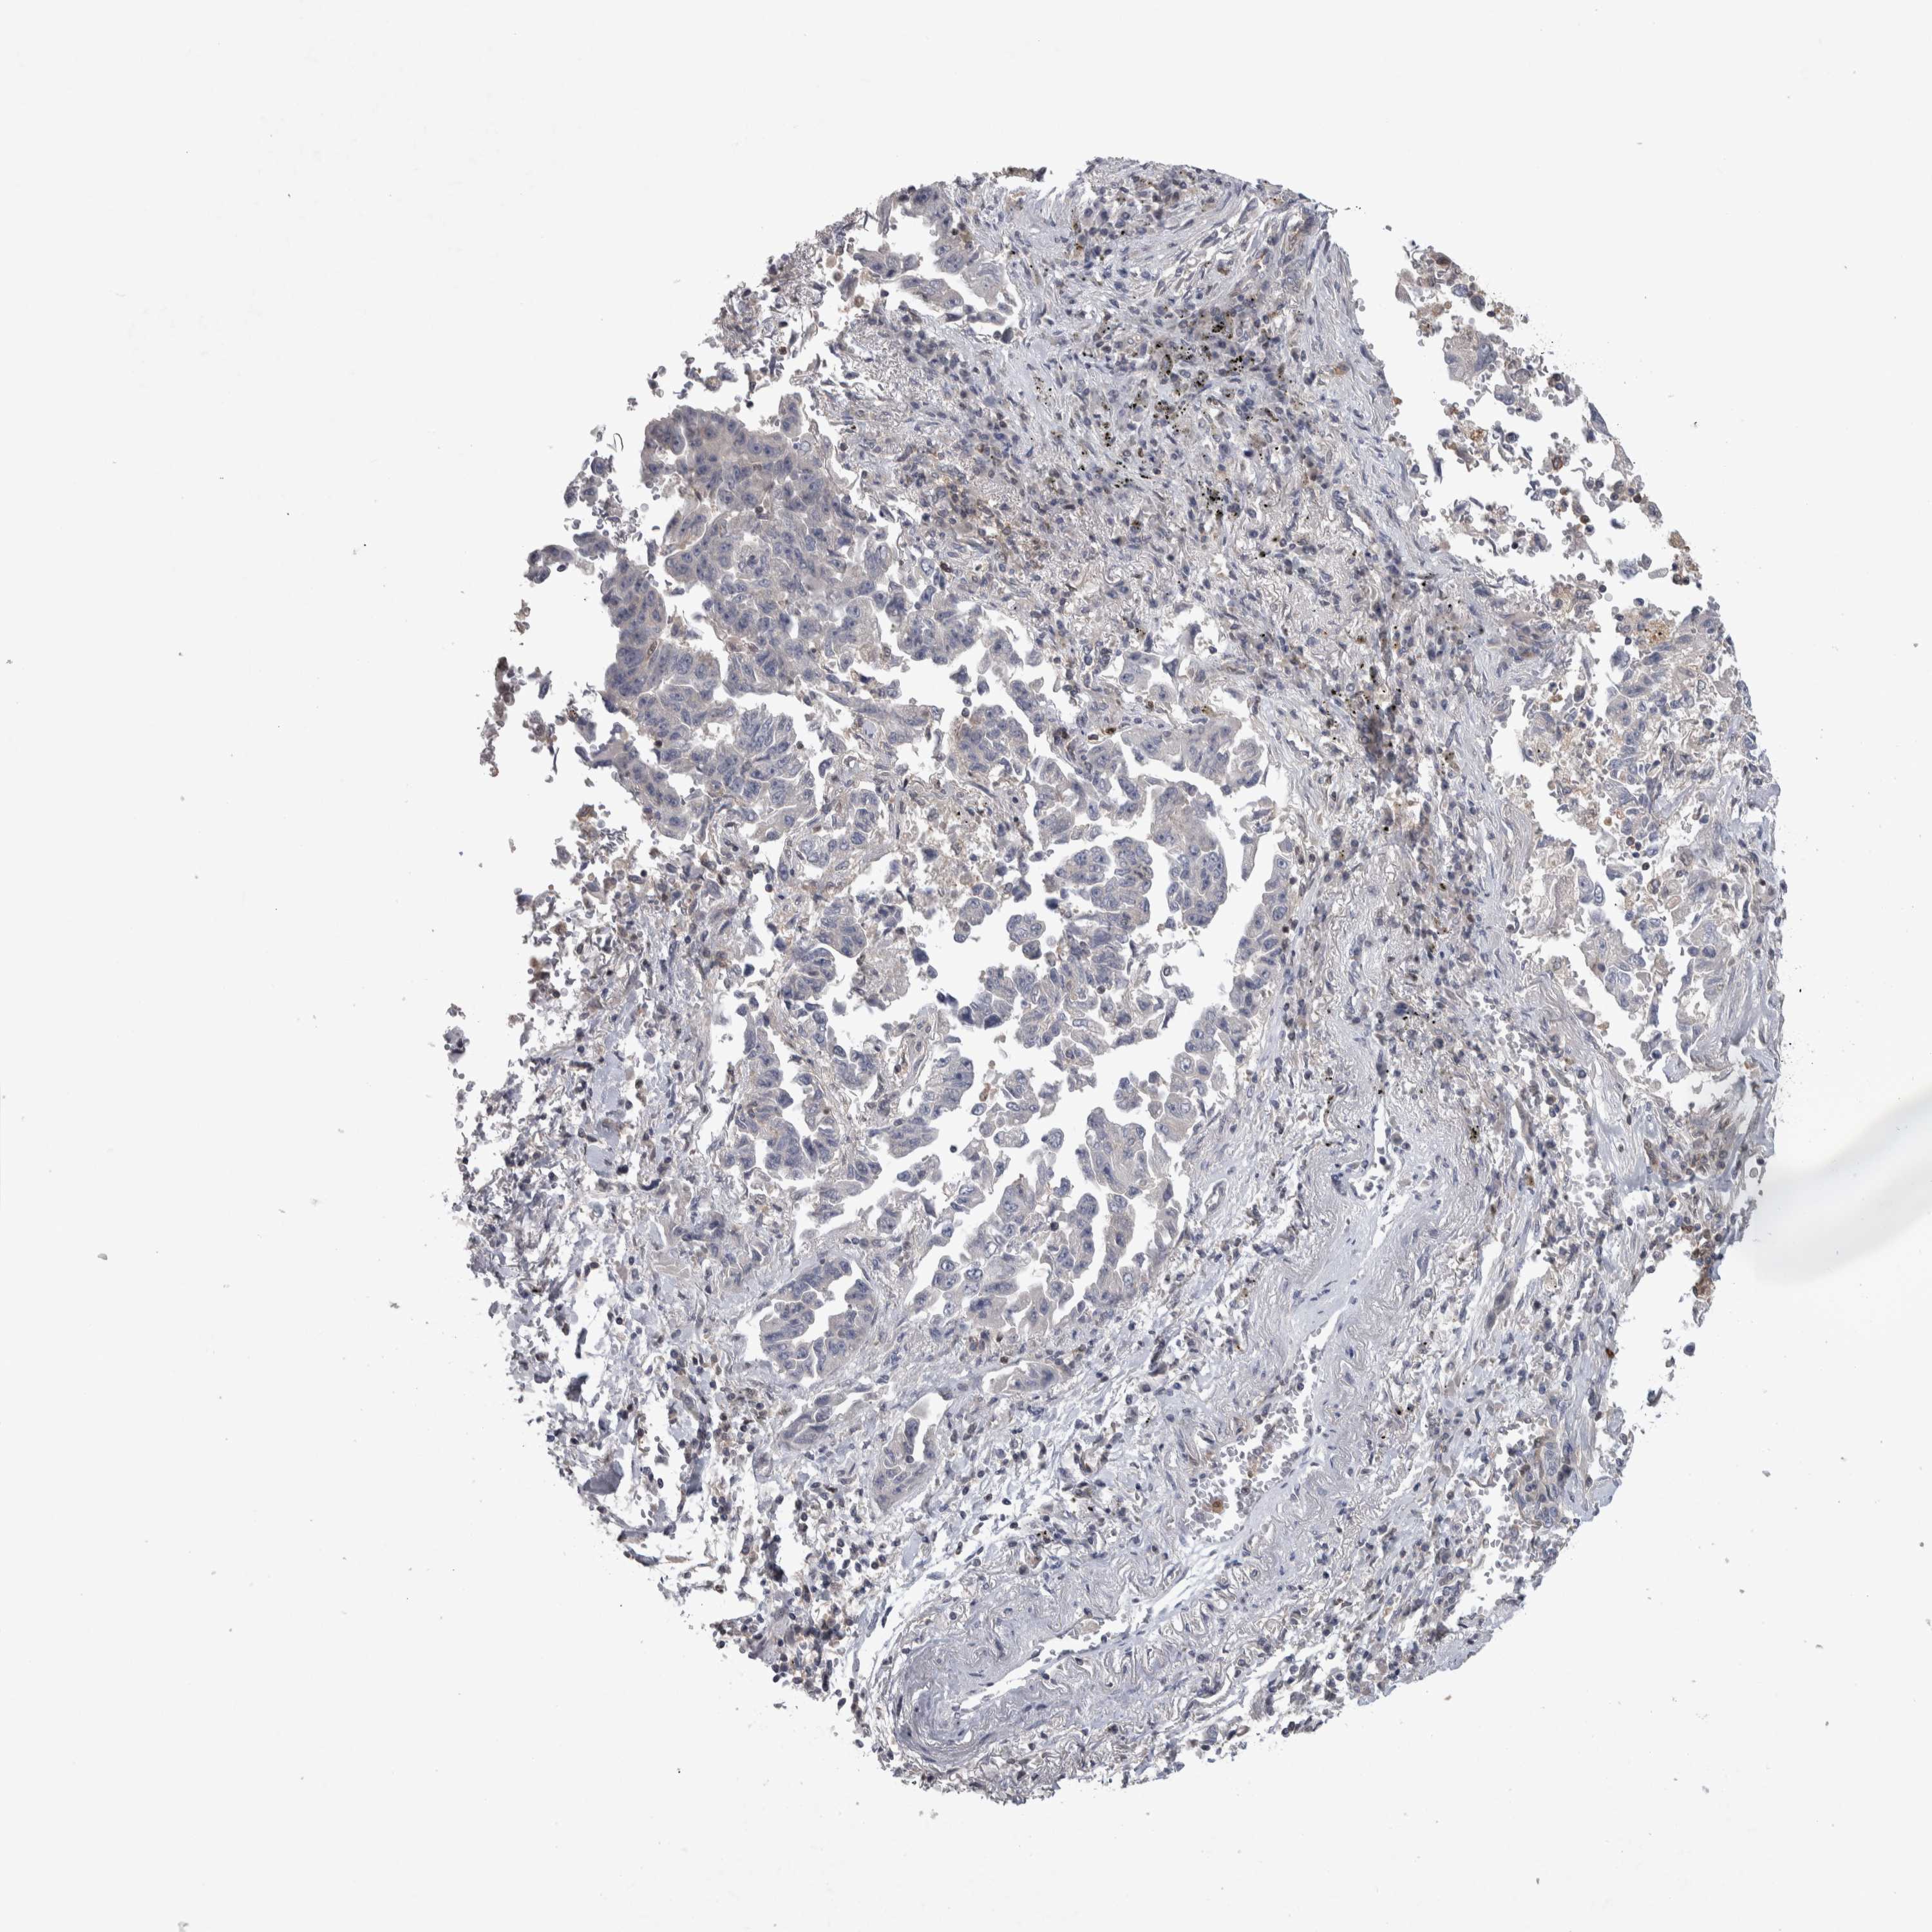

LUNG ADENOCARCINOMA (VALIDATION) - Interactive survival scatter ploti

The Survival Scatter plot shows the clinical status (i.e. dead or alive) for all individuals in the patient cohort, based on the same data that underlies the corresponding Kaplan-Meier plots. Patients that are alive at last time for follow-up are shown in blue and patients who have died during the study are shown in red.

The x-axis shows the expression levels (FPKM) of the investigated gene in the tumor tissue at the time of diagnosis. The y-axis shows the follow-up time after diagnosis (years). Both axes are complimented with kernel density curves demonstrating the data density over the axes. The top density plot shows the expression levels (FPKM) distribution among dead (red) and alive patients (blue). The right density plot shows the data density of the survived years of dead patients with high and low expression levels respectively, stratified using the cutoff indicated by the vertical dashed line through the Survival Scatter plot. This cutoff is automatically defined based on the FPKM cutoff that minimizes the p-score. The cutoff can be changed by dragging the vertical line or by entering a cutoff value in the square labeled "Current cut-off".

Under the Survival Scatter plot the p-score landscape (black curve; left axis) is shown together with dead median separation (red curve; right axis). Dead median separation is the difference in median mRNA expression between patients who have died with high and low expression, respectively. It is calculated as follows: median FPKM expression of dead patients with high expression - median FPKM expression of dead patients with low expression. This is intended to aid the user in visually exploring custom cutoffs and the associated p-scores and dead median separation.

Individual patient data is displayed and can be filtered by clicking on one or more of the category buttons on the top of the page. Categories describing expression level and patient information include: high, low, alive, dead, female, male and tumor stages. The scale of the x-axis can be toggled between linear and log-scale by clicking on the "x log" button. Mouse-over function shows TCGA ID, patient information and mRNA expression (FPKM) for each patient.

& Survival analysisi

Kaplan-Meier plots summarize results from analysis of correlation between mRNA expression level and patient survival. Patients were divided based on level of expression into one of the two groups "low" (under cut off) or "high" (over cut off). X-axis shows time for survival (years) and y-axis shows the probability of survival, where 1.0 corresponds to 100 percent.

NFKB2 is not prognostic in Lung Adenocarcinoma (validation)

Current cut offi

Current cut-off shows the cut-off (FPKM) currently selected. It may be changed manually. When the current cut-off is changed, the vertical dashed line indicating cut-off, the interactive survival scatter plot and the Kaplan-Meier curve will be automatically adjusted to show results accordingly.

:

Best expression cut offi

Based on the FPKM value of each gene, patients were classified into two groups and association between prognosis (survival) and gene expression (FPKM) was examined. The best expression cut-off refers the FPKM value that yields maximal difference with regard to survival between the two groups at the lowest log-rank P-value. Best expression cut-off was selected based on survival analysis .

When clicking on this number, the vertical dashed line indicating cut-off, the interactive survival plot, and the Kaplan-Meier curve will be adjusted to show results based on the best expression cut-off.

: 21.24

Median expressioni

Median expression refers to the median FPKM value calculated based on the gene expression (FPKM) data from all patients in this dataset. When clicking on this number, the vertical dashed line indicating cut-off, the interactive survival plot, and the Kaplan-Meier curve will be adjusted to show results based on the median expression.

: N/A

Median follow up timei

Median follow up time refers to the median time (years) after diagnosis with this type of cancer, based on clinical data from all patients in this dataset.

P scorei

Log-rank P value for Kaplan-Meier plot showing results from analysis of correlation between mRNA expression level and patient survival.

N/A

5-year survival highi

5-year survival for patients with higher expression than the expression cutoff.

For melanoma and glioma, 3-year survival is shown.

5-year survival lowi

5-year survival for patients with lower expression than the expression cutoff.

TCGA RNA samplesi

RNA-seq data is reported as average FPKM (number Fragments Per Kilobase of exon per Million reads), generated by the The Cancer Genome Atlas (TCGA) .

Normal distribution across the dataset is visualized with box plots, shown as median and 25th and 75th percentiles. Points are displayed as outliers if they are above or below 1.5 times the interquartile range. FPKM values of the individual samples are presented next to the box plot.

Average pTPM 14.7

Number of samples 105